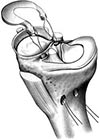

Il legamento crociato anteriore non può essere suturato; è necessario ricostruirlo utilizzando innesti tendinei che fungono da impalcatura su cui si formerà un neo-legamento. Gli innesti autologhi (prelevati dal paziente stesso) più frequentemente utilizzati sono il tendine rotuleo e i tendini flessori del ginocchio (gracile e semitendinoso). Si possono eventualmente utilizzare anche innesti omologhi (da cadavere).

Ciascuna fonte d’innesto presenta vantaggi e svantaggi; la scelta del tipo di trapianto viene fatta dal chirurgo insieme al paziente sulla base di un’attenta valutazione.

La tecnica chirurgica prevede la preparazione di 2 tunnel ossei (tibiale e femorale) entro cui viene fatto passare il trapianto debitamente preparato che verrà poi fissato con viti o pin (metallici o di materiale riassorbibile).